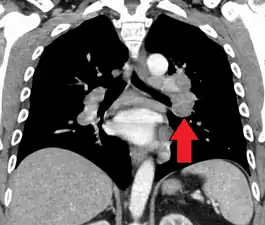

Hilar adenopathy especially on the person's left (AP CXR)

Hilar adenopathy especially on the person's left (lateral CXR)

Hilar adenopathy especially on the person's left (coronal CT)